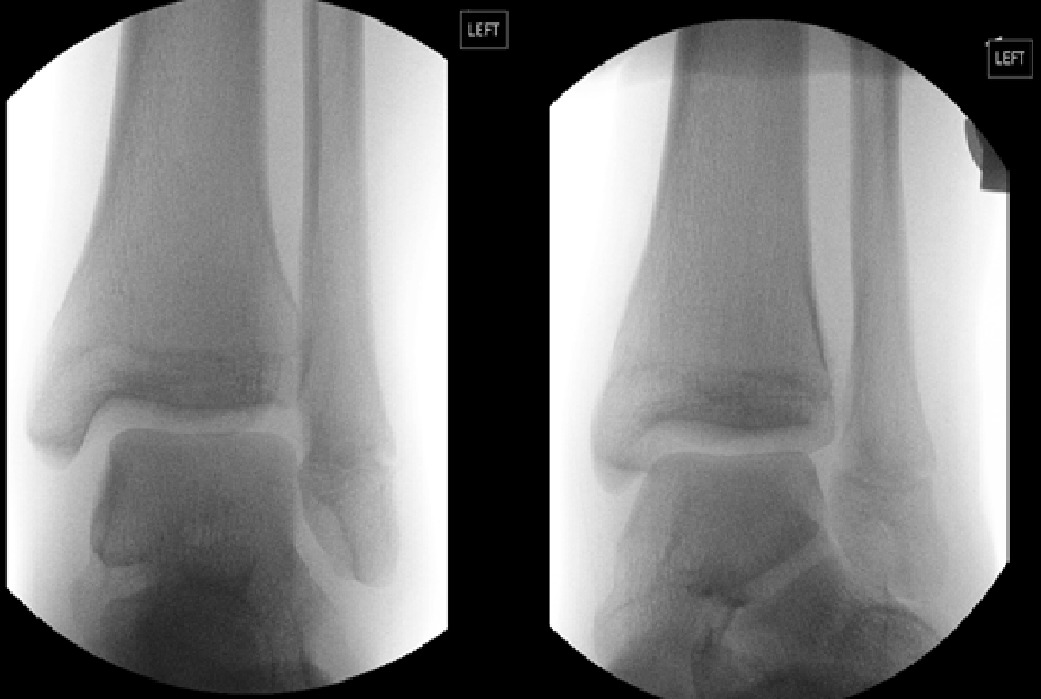

On the latest presentation, there were no open wounds or neurovascular compromise. There was a significant ankle joint effusion with tenderness of both lateral and medial malleoli of both ankles. The patient was able to weight-bear independently, despite significant pain. On plain radiograph no fracture was noted. The mortise view of both ankles revealed loss of tibiofibular overlap. With the provisional diagnosis of bilateral acute syndesmosis injury, the patient underwent an examination under anaesthesia (EUA) of both ankles.

Both ankles demonstrated widening of the syndesmosis intervals when Cotton stress test was applied (Figure 1 and 2). The ankles were reduced under image intensifier and each ankle had definitive percutaneous fixation using two 3.5mm cortical screws (Synthes). Postoperatively, the patient remained non-weightbearing for 6 weeks. He was allowed to weight-bear as tolerated after 6 weeks in bilateral CAM boots and commenced gentle range of motion exercises with a physiotherapist. Radiographs at 3-months indicated enlocated and stable ankle joints with no failure of syndesmotic fixation (Figure 3). The patient underwent hardware removal and further external rotation stress tests at 3 months. There was no widening of either syndesmosis intervals. The patient progressed well with physiotherapy and was able to return to competitive basketball within 4 weeks of hardware removal. At 16 weeks after the index injury, the patient was able to achieve 30-degree flexion and 45-degree extension of both ankles and VAS pain score was 0 for both ankles at time of follow-up.